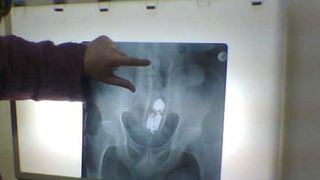

Medicii au avut un șoc când au observat că tânărul avea blocat în anus un tub de deodorant. Bărbatul de 23 de ani a declarat că se afla acasă cu iubita și s-a așezat din neatenție pe tub, potrivit realitateaoltului.ro.

Ajuns la spital, tânărul a fost operat de urgență. Intervenţia a avut loc zona abdominală, deoarece era plasat la palpare în zona abdominală, încă din momentul preluării pacientului de către echipajul de salvare. Bărbatul a intitulat întreaga situație drept un ”accident casnic”.